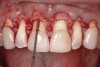

Following anesthesia, a scalloped incision was made on the keratinized tissue (Figure 3). In the interproximal area, a papilla-sparing incision was made. A full-thickness flap was raised to give access to the underlying bone (Figure 4). Both osteoplasty and ostectomy were performed to position the bone crest approximately 2 mm to 3 mm from the CEJ (Figure 5). The gingival tissue was repositioned, coinciding with the initial labial incision and the interproximal papilla. Interrupted sutures were placed (Figure 6), which were removed 7 days following the surgery.

Fig 5. Surgical field after osteoplasty and ostectomy.

Figure 5